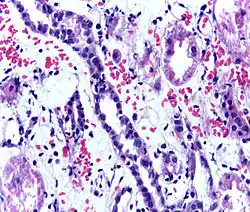

Presence of lymphocytes within the tubular epithelium, attesting to acute cellular rejection of a renal graft. Biopsy sample.